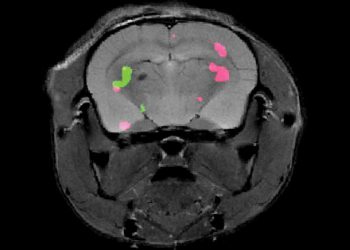

לו ניתן היה, למשל, לסמן בצבעים את ביטוי הגנים בתאי הגוף, היו נפרסים לנגד עינינו תהליכים ביולוגיים חיוניים שכיום נסתרים ...